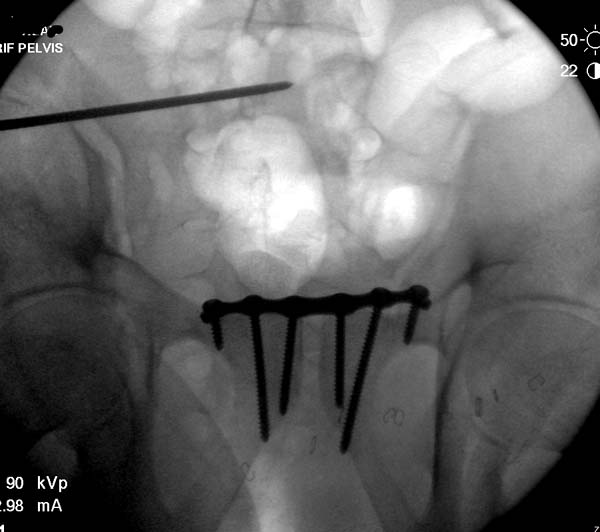

Техника репозиции вытяжением работает намного лучше, когда конечность в

согнутом положении, потому что нейтрализируются абдоминальные мышцы.

Вместо больших грузов, сгибание лучший прием для репозиции. А все

остальные методы: фиксация половины таза к столу и опускание головной

части вниз, создают хаос в операционной!

Здесь примеры фиксации с различными вариантами.... .